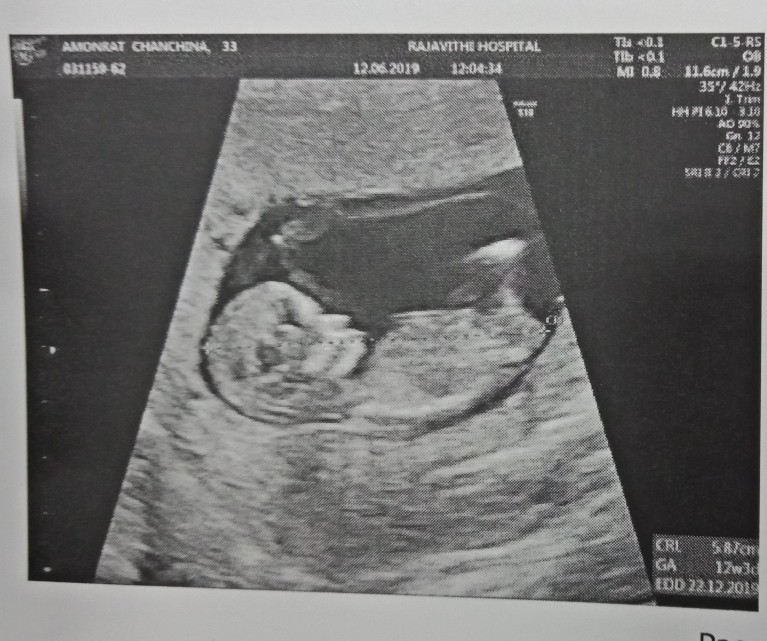

12w5dจร้า ปัจจุบัน19w3dจ้า

12W 5d ล่าสุดเลยค่ะ